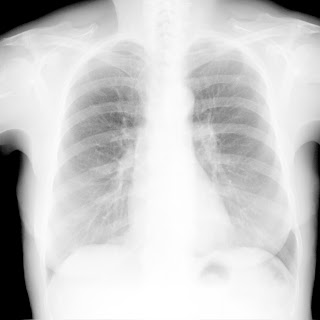

Флюорограма №73

Легені без вогнищево - інфільтративних змін. Корені не змінені. Синуси вільні. Серце норма.